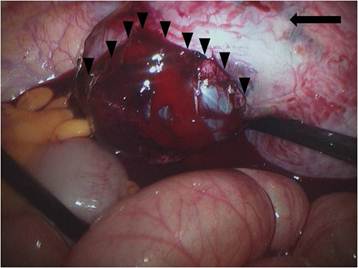

A 35-year-old pregnant woman (gravida 5, para 2), with a history of 2 vaginal term deliveries and 2 spontaneous abortions treated by dilatation and curettage, was admitted to the emergency department because of sudden severe abdominal pain. At admission, the gestational age was calculated to be 14 weeks by sonography (Fig. 1); she had not received any antenatal care. During physical examination, abdominal tenderness was noted; in addition, her blood pressure was 110/60 mm Hg; heart rate, 98 beats/min; and body temperature, 36.1°C.

Figure 1

Ultrasound examination showing intrauterine pregnancy at 14 weeks gestation.

Ultrasound examination revealed moderate accumulation of free fluid in the peritoneal cavity. In addition, the placenta was located at the upper anterior uterine wall, the fetal heart rate was 171 beats/min, and uterine contractions were absent. Laboratory analysis showed a hemoglobin level of 10.3 g/dl and an elevated white blood cell count of 17550 cells/mm3. Because the pregnancy was intrauterine and not otherwise, our initial clinical impression was appendicitis; however, in the absence of fever, the diagnosis of appendicitis could not be confirmed. To diagnose the cause of continuous severe abdominal pain, we decided to conduct diagnostic laparoscopy to exclude appendicitis, cholecystitis, and peritonitis.